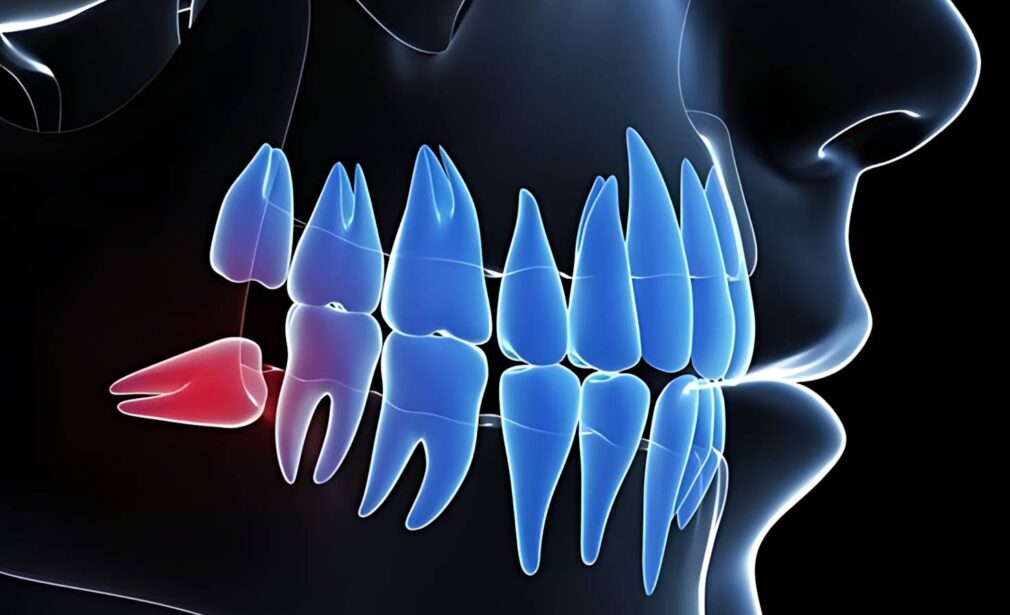

Perawatan akar dan saraf gigi (disebut juga Perawatan Saluran Akar / PSA / Root Canal Treatment) adalah tindakan medis untuk membersihkan infeksi pada bagian dalam gigi (pulpa/saraf), kemudian menutupnya kembali agar gigi tetap bisa dipertahankan dan tidak perlu dicabut.

Di dalam gigi terdapat pulpa yang berisi:

- Saraf

- Pembuluh darah

- Jaringan lunak

Jika bagian ini terinfeksi atau mati, maka perlu dilakukan perawatan saluran akar untuk: